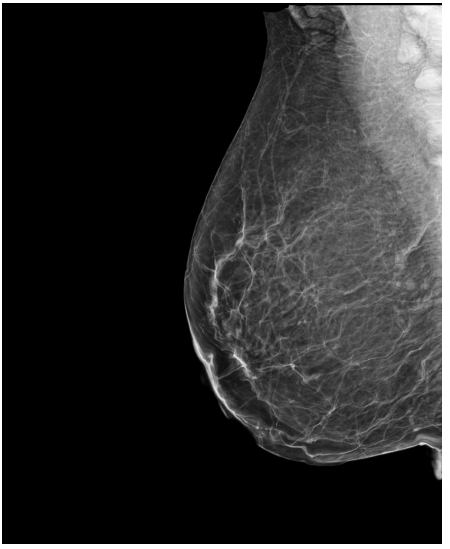

4.3 Pre-processing

The EMBED and CSAW-CC datasets originally consist of images in DICOM format, which are converted into 16-bit grayscale PNG images for consistency and compatibility. Following the pre-processing procedure outlined in (Yala et al.,, 2021), we enhanced image quality and removed background artifacts—such as textual annotations commonly present in mammography images—by applying a contour detection procedure. All contours in the image are detected, and only the largest contour, corresponding to the breast tissue, is retained. This contour is then used to create a mask that isolates the breast region from the background. The isolated breast image is resized to a size of 1664×20481664\times 2048 pixels while preserving the aspect ratio. Finally, the resized image is normalized and converted to a 16-bit format.